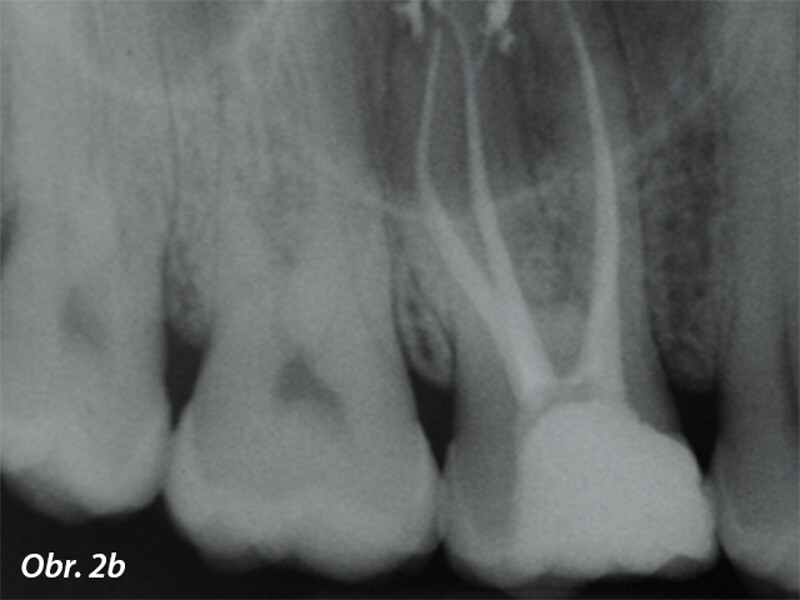

Vyplachování zahnutých kanálků